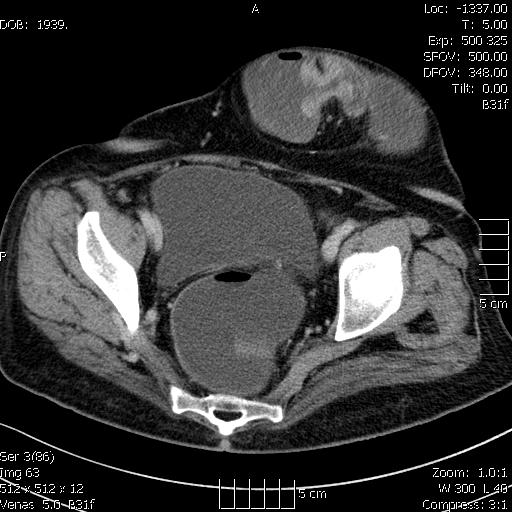

A vastagbelek vízzel töltve (hydro-colo CT készült, mert a colonoscopia nem volt végig kivitelezhető)